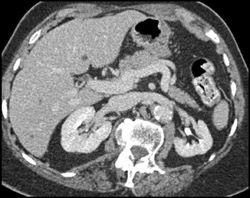

Renal Infarction